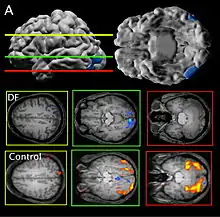

DF Lesion

Patient DF's brain damage resulted from hypoxia due to carbon monoxide poisoning.[2] The lateral occipital cortex (LOC) in her brain is severely damaged and shows no activation presented with line drawings of common objects where healthy people usually do. Moreover, there is a reduction of white matter connections between LOC and other areas.[3] There is also some shrinkage in the intraparietal sulcus, often implicated in the dorsal stream for visuomotor control. The fusiform face area is intact. This would suggest the problem in DF's perception is disconnectivity between higher and lower order functioning.[2]

DF does not benefit from haptic feedback—allowing her to pick up an object does not let her better estimate its width next time.[4] DF also does not use visual information about her grasp: when she can only see her grip in a distorted mirror, her performance does not change.[2] Consistent with all of this, brain imaging has shown no response to line drawings in her ventral stream. Furthermore, according to fMRI studies, the intraparietal sulcus showed preference for grasping motions over reaching motions—actually grabbing an object, in both DF and control patients, activates the intraparietal sulcus more than reaching.[2]